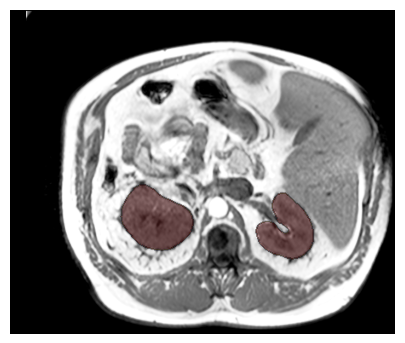

Purpose: To introduce a deep learning model capable of multi-organ segmentation in MRI scans, offering a solution to the current limitations in MRI analysis due to challenges in resolution, standardized intensity values, and variability in sequences. Materials and Methods: he model was trained on 1,200 manually annotated MRI scans from the UK Biobank, 221 in-house MRI scans and 1228 CT scans, leveraging cross-modality transfer learning from CT segmentation models. A human-in-the-loop annotation workflow was employed to efficiently create high-quality segmentations. The model's performance was evaluated on NAKO and the AMOS22 dataset containing 600 and 60 MRI examinations. Dice Similarity Coefficient (DSC) and Hausdorff Distance (HD) was used to assess segmentation accuracy. The model will be open sourced. Results: The model showcased high accuracy in segmenting well-defined organs, achieving Dice Similarity Coefficient (DSC) scores of 0.97 for the right and left lungs, and 0.95 for the heart. It also demonstrated robustness in organs like the liver (DSC: 0.96) and kidneys (DSC: 0.95 left, 0.95 right), which present more variability. However, segmentation of smaller and complex structures such as the portal and splenic veins (DSC: 0.54) and adrenal glands (DSC: 0.65 left, 0.61 right) revealed the need for further model optimization. Conclusion: The proposed model is a robust, tool for accurate segmentation of 40 anatomical structures in MRI and CT images. By leveraging cross-modality learning and interactive annotation, the model achieves strong performance and generalizability across diverse datasets, making it a valuable resource for researchers and clinicians. It is open source and can be downloaded from https://github.com/hhaentze/MRSegmentator.